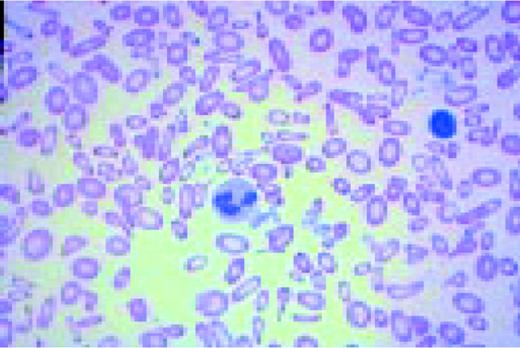

Slide E10

Low-power view of the peripheral blood in a patient with severe iron deficiency anemia. A normal lymphocyte is present (for comparison purposes) to the right of center. Marked anisocytosis and poikilocytosis can be appreciated as can microcytosis and hypochromiaFIG106